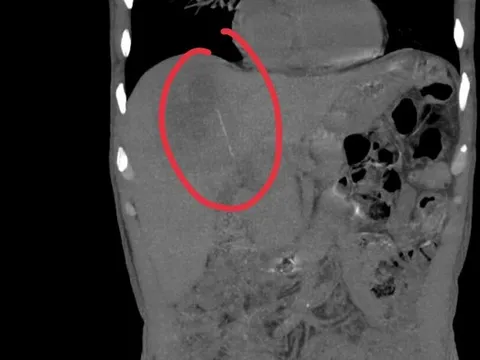

Sau vài lần bị cho uống rượu, đứa trẻ xuất hiện các triệu chứng lờ đờ, ít vận động, da bắt đầu vàng da. Theo bác sĩ, gan của bé đã bị tổn thương rõ rệt, tiệm cận suy gan.

Bé 5 tháng tuổi tổn thương gan nghiêm trọng vì người lớn dùng đũa chấm vào rượu cho bé nếm thử- Ảnh 1.

Ảnh Minh Họa

1. Tổn thương gan và dạ dày: rượu kích thích mạnh, gây suy giảm chức năng gan, rối loạn tiêu hóa.